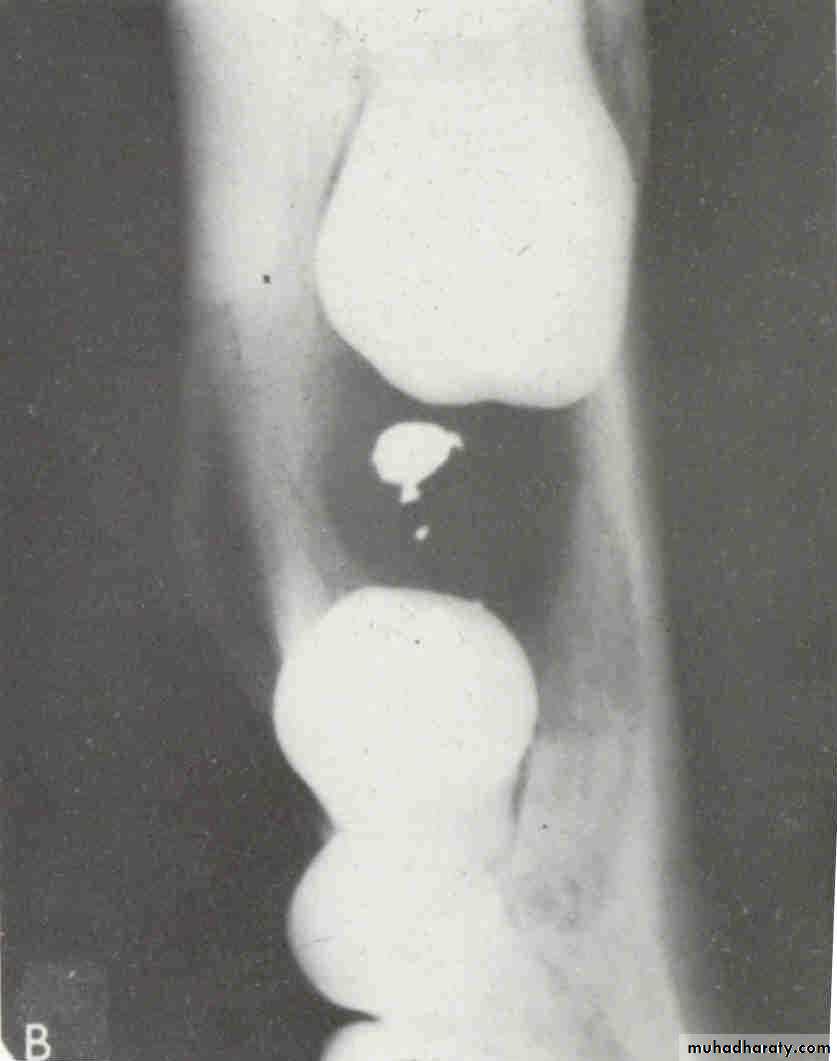

Cystic ameloblastoma displaced IDC (odontogenic origin)

Epicenter coronal to tooth

(odontogenic epithelium )